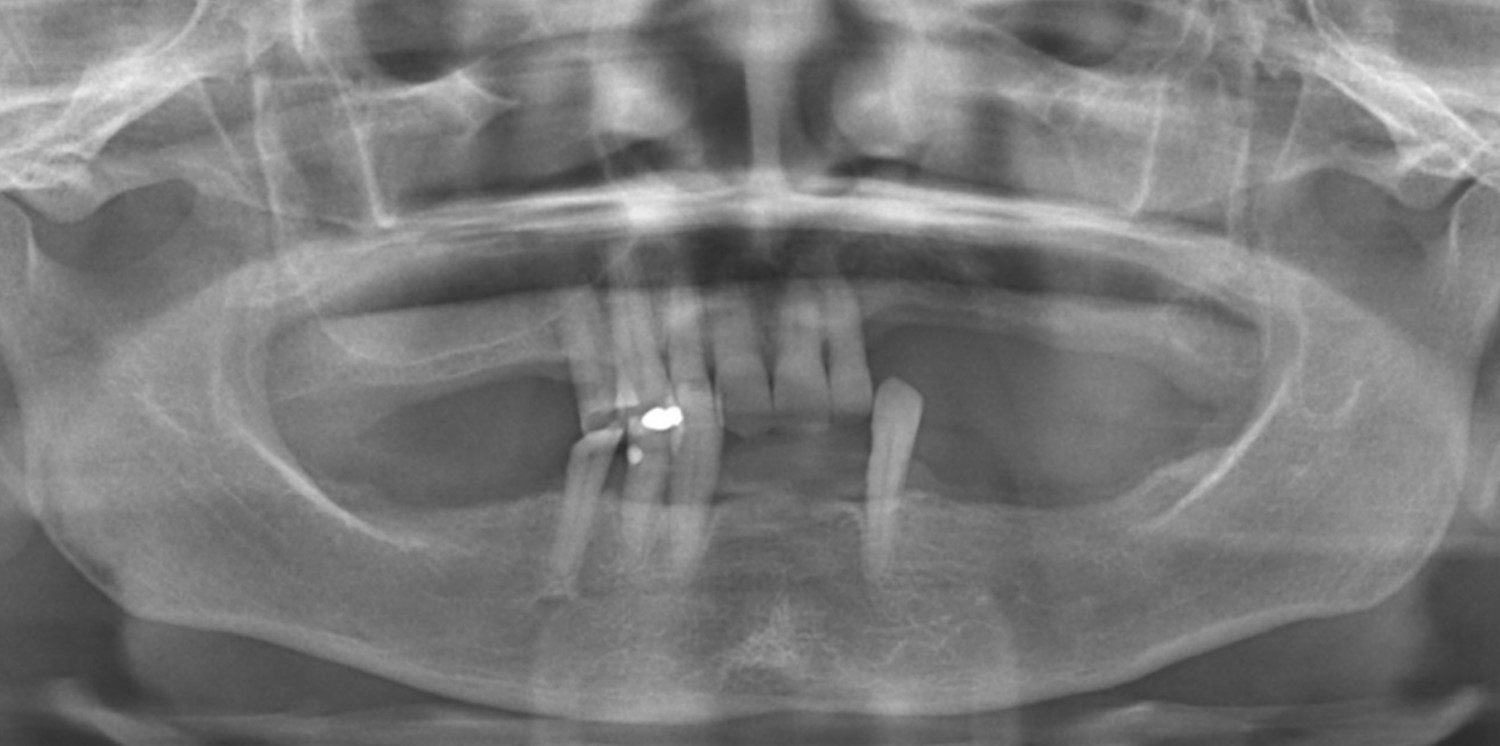

Fig. 2 – Radiografia inicial

Na análise radiográfica, constatou-se pneumatização do seio maxilar direito em direção ao pilar canino. No lado esquerdo, a extensão da pneumatização poderia inviabilizar a realização da técnica sem enxertos ósseos. Para garantir a instalação precisa e segura do implante, foi realizado um acesso lateral à janela do seio maxilar, permitindo o tratamento da parede anterior do seio com uma sonda para determinar a posição ideal do implante distal. Aproveitou-se o máximo de osso disponível, tangenciando o seio maxilar e eliminando a necessidade de enxertos ósseos. Foi escolhido o sistema Vezza da FGM, devido a geometria que fornece alta estabilidade primária e oferece conexão hexagonal externa universal, ou seja, bastante versátil.

Após a perfuração inicial com broca lança de 15 mm para os implantes distais e 11 mm para os anteriores, a perfuração com broca 2,4 nos mesmos comprimentos. paralelizadores foram utilizados para verificar o polígono formado e a posição dos implantes. A perfuração seguinte com broca 3.4 e, após, com broca 3.9, a onde foi realizado subperfuração em comprimento (50%), garantindo melhor estabilidade primária. Foram instalados implantes Vezza de 4,3×15 mm na região posterior da maxila e de 4,3×11 mm na região anterior.